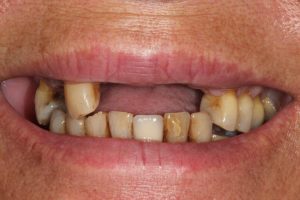

Full Mouth Rehabilitation

Full mouth Treatment – missing upper front teeth and mispositioned implants in the Lower left side meant planning was key here to get the desired result. Implants were placed to replace the missing teeth, veneers/crowns on the remaining upper teeth allowing an improvement in overall shape and colour, and the implant crowns on the lower left were change to bring into the line of the bite.